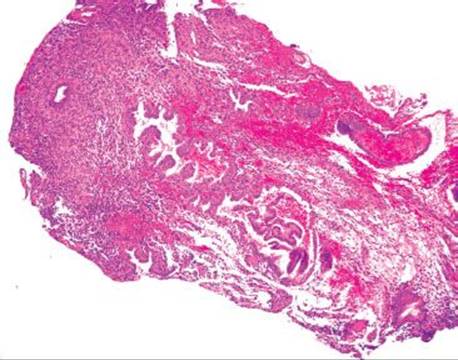

Figure 4.271 Endometriosis. This consultation case originated from a 25-year-old woman with a bleeding rectal mass. It was clinically ominous appearing, leading the surgeon to inform the patient that the lesion was most likely malignant. Based on the patient’s young age, the family asked for the case to be externally reviewed.

Endometriosis is the presence of at least two of the three following features outside of the uterus: endometrial glands, stroma, and hemorrhage (Figs. 4.271–4.273). Up to 37% of women with endometriosis have intestinal involvement, and any layer of the bowel can be involved. The clinicopathologic presentation is diverse and presentations can overlap with appendicitis, IBD, diverticular disease, infectious colitis, a surgical acute abdomen, malignancy.125–128 Endometriosis involving the rectum commonly presents as bloody diarrhea. Associated pathologic findings can include strictures, ulceration, fissures, ischemia, and intussusception.125 The lesions can appear as polyps or bleeding mass lesions, raising clinical concerns for malignancy. The overlying colonic epithelium can be markedly reactive and mimic dysplasia, leading to the misdiagnosis of colonic adenocarcinoma. Occasionally, only the stromal component is seen and a diagnosis of sarcoma is entertained. In these cases, usually the endometrial glands can be identified on deeper sections. Confirmatory immunohistochemical stains include ER and PR to highlight the glandular components and CD10 to highlight the endometrial stroma.